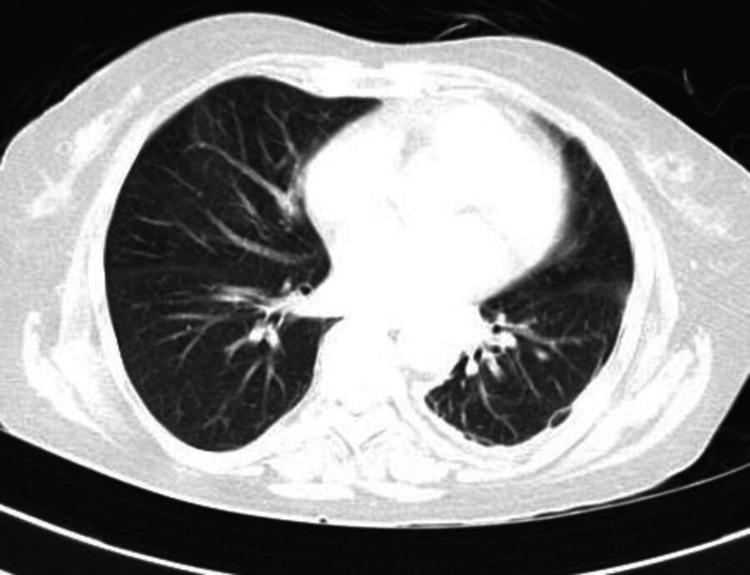

Chemical pneumonitis caused by dimethanol and glutaraldehyde exposure is a serious medical condition that requires prompt and effective treatment. As per a literature search in Google Scholar, PubMed, and Scopus, this is the first instance of chemical pneumonitis caused after fumigation with dimethanol and glutaraldehyde inhalation. This article discusses the factors that can contribute to the development of chemical pneumonitis and outlines the diagnostic and treatment options available to healthcare professionals. By understanding the causes and consequences of dimethanol- and glutaraldehyde-induced chemical pneumonitis, medical professionals can provide better care to their patients and help prevent future cases of this potentially life-threatening condition. This describes a case of a 60-year-old female who presented to the emergency department complaining of acute onset of shortness of breath approximately 48 hours after being exposed to dimethanol and glutaraldehyde while working in intensive care. After 13 days, the patient's symptoms subsided and she was discharged. On follow-up, after 1 month, there was a marked resolution of the initial symptoms.

接触二甲醇和戊二醛引起的化学性肺炎是一种严重的病症,需要及时有效的治疗。根据在谷歌学术、PubMed和Scopus上的文献检索,这是首次因吸入二甲醇和戊二醛熏蒸后引发化学性肺炎的案例。本文讨论了可能导致化学性肺炎发生的因素,并概述了医疗专业人员可用的诊断和治疗方案。通过了解二甲醇和戊二醛引起的化学性肺炎的病因和后果,医学专业人员可以为患者提供更好的护理,并有助于预防这种潜在的危及生命病症的未来病例。本文描述了一名60岁女性的病例,她在重症监护病房工作时接触二甲醇和戊二醛后约48小时出现急性呼吸急促,前往急诊科就诊。13天后,患者症状消退并出院。在1个月后的随访中,初始症状明显缓解。